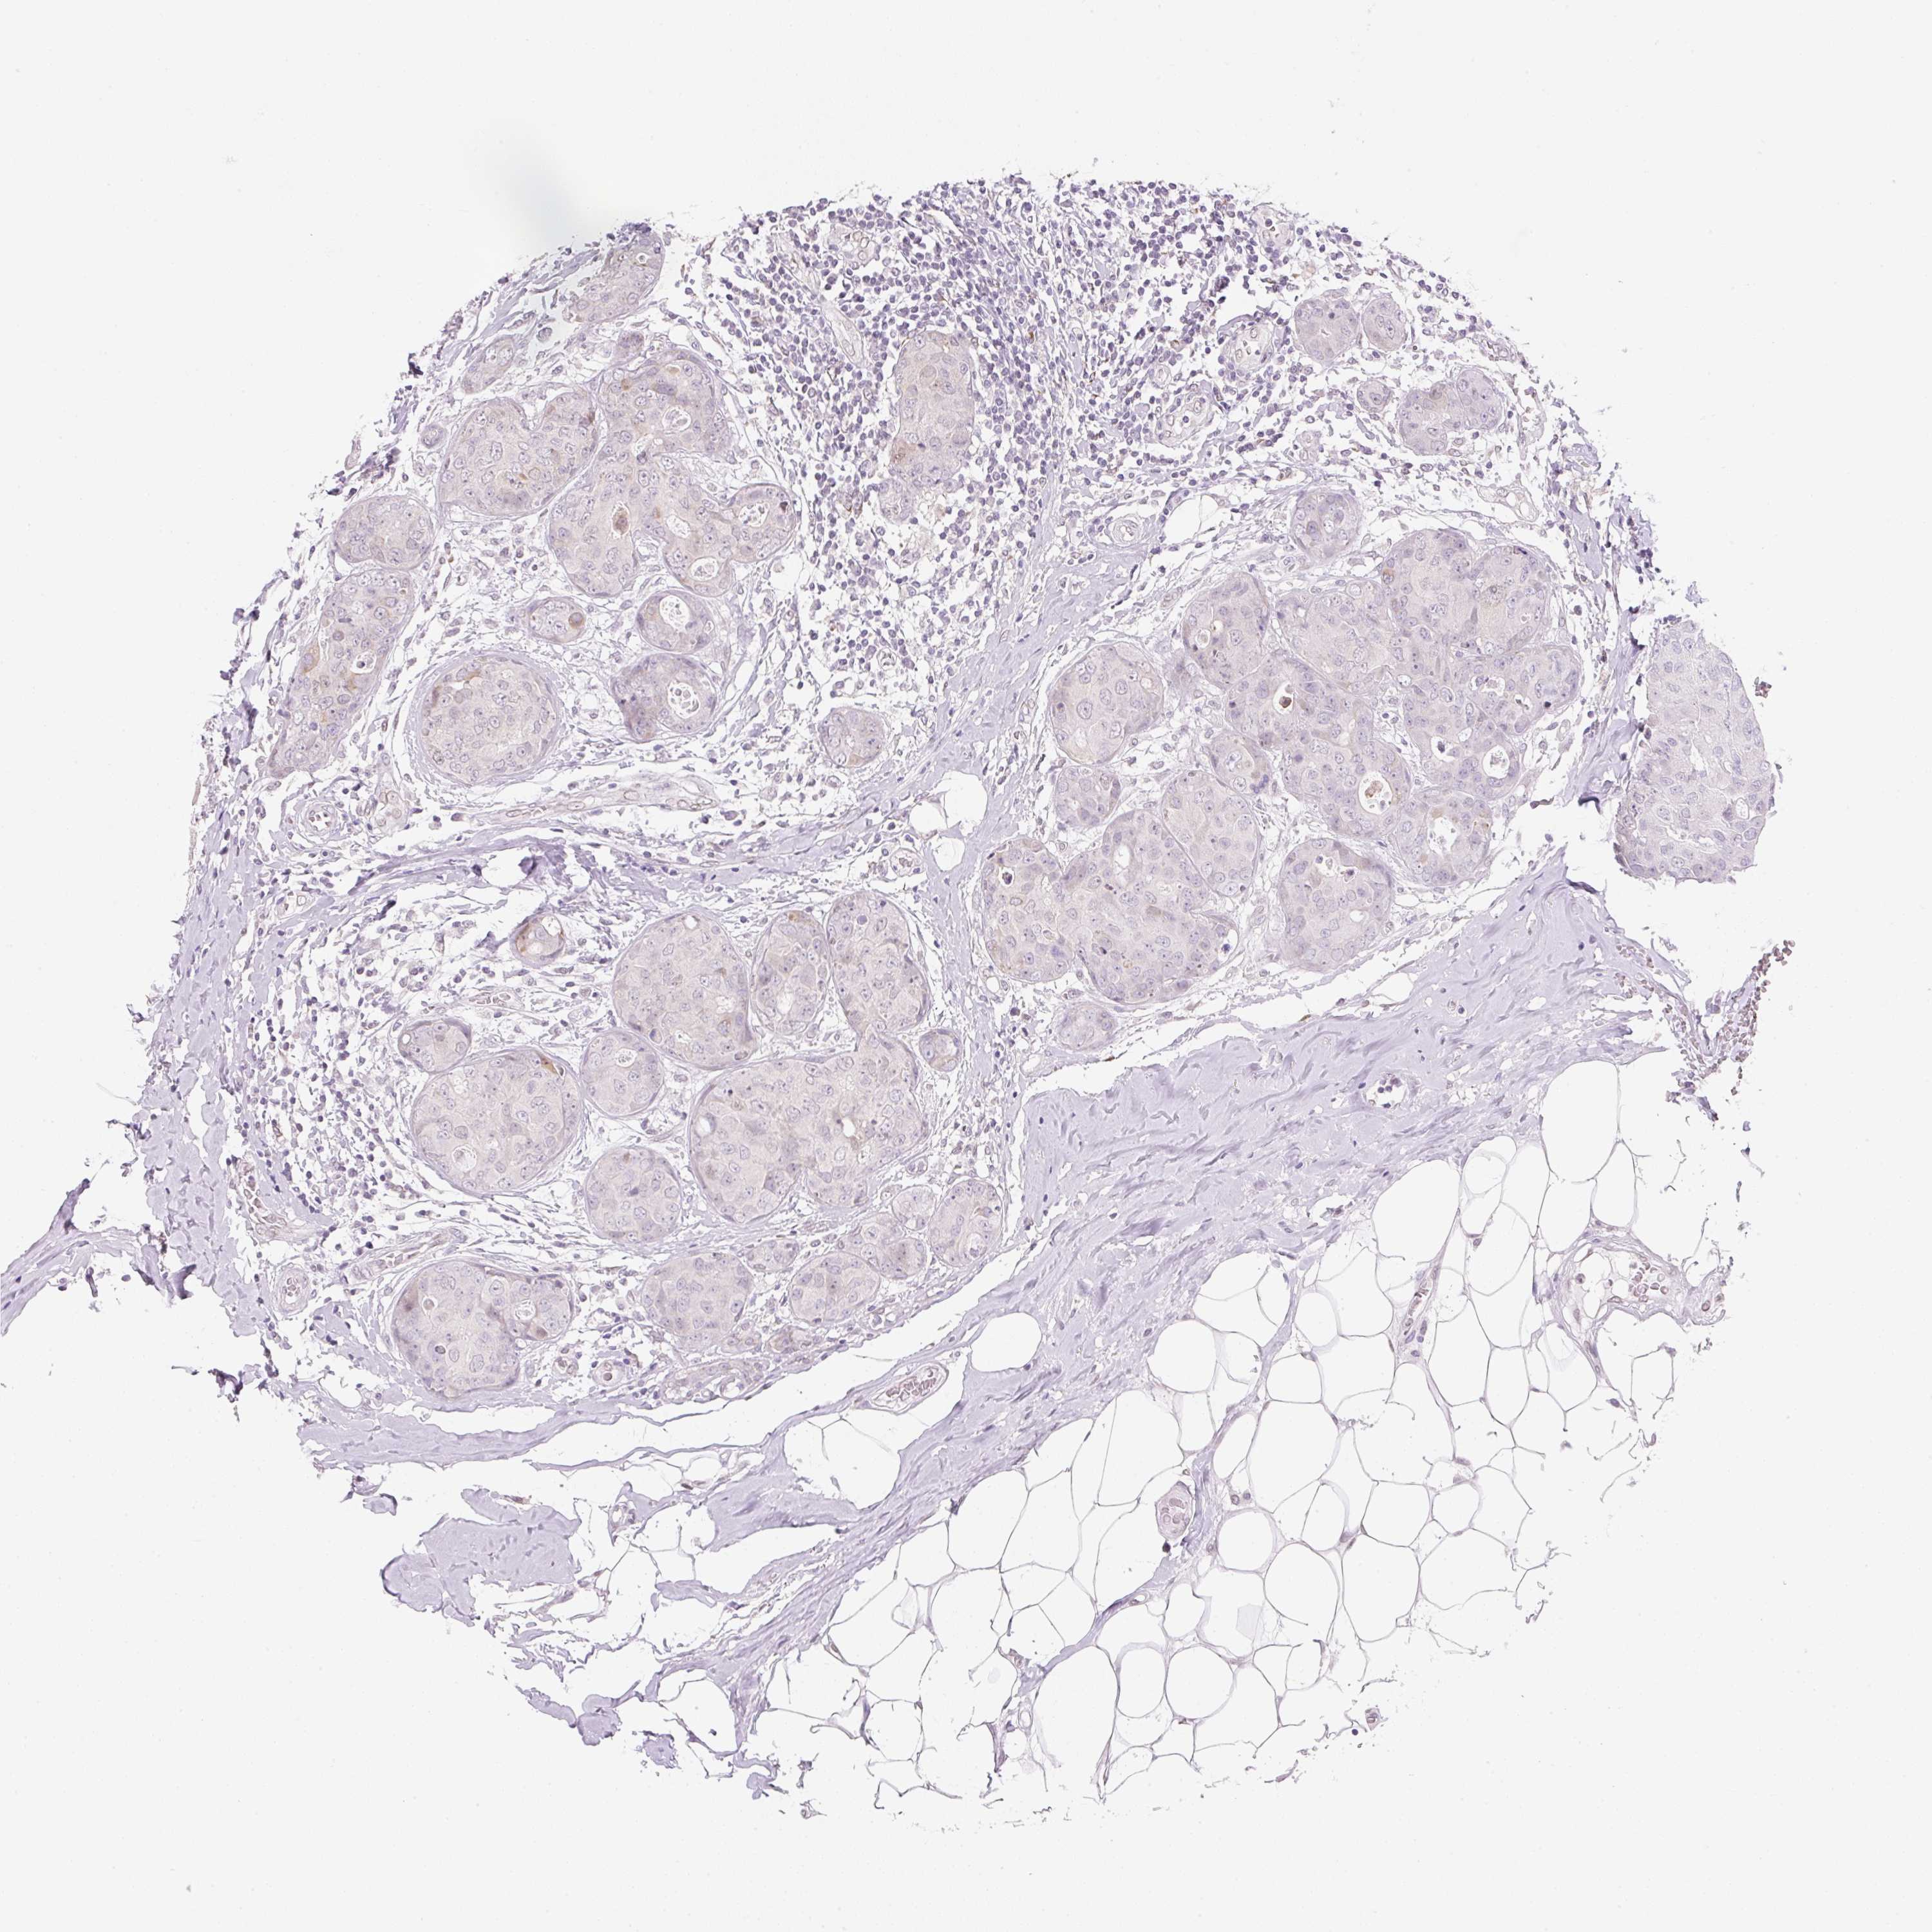

CANCER BREAST CANCER Show tissue menu

BRCA TCGA BRCA VALIDATION PROTEIN EXPRESSION